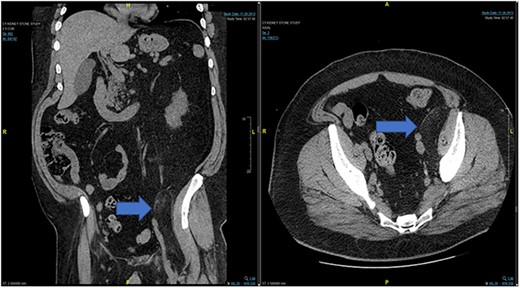

In the emergency department, vital signs were remarkable for elevated blood pressure of 166/81, but otherwise stable and afebrile. WBC count was elevated at 15.4 with left shift and hemoglobin was low at 9.6. Complete Metabolic Panel was notable for hyponatremia of 128, and mildly elevated BUN/serum creatinine of 26/1.5 which was slightly higher than his baseline of 17/1.3. Liver function tests were unremarkable. UA showed likely UTI with positive esterase, high RBC/WBC and bacteria and protein. A CT of the abdomen and pelvis was done, showing a left non-obstructing kidney stone and a left retroperitoneal fat density with stranding along the left iliopsoas measuring 12.6 × 8.1 cm × 3.7 cm, which was described as possibly a part of infectious or malignant process (Fig. 5). Subsequently, patient’s prior CT scans were available to be reviewed and it showed the same lipomatous mass 9 years earlier. (Fig. 6). Given the patient’s symptoms of left lower extremity pain and the possibility that the mass was responsible, a CT-guided core biopsy was ordered for diagnosis to rule out a malignant process as operative intervention was being contemplated. Pathology report of the core biopsy showed lobules of univacuolated adipocytes divided by thin septa. There were frequent multivacuolated adipocytes with small round nuclei, reminiscent of brown fat cells. No enlarged hyperchromatic cells, mitotic figures nor necrosis are seen. The findings supported the diagnosis of the lipoma variant of hibernoma (Fig. 4). Given the chronicity of the mass, the near identical size over 9 years and the diagnosis made from core biopsy, it was determined that the hibernoma was not the likely source of the patient’s LLE pain and hence the mass was not excised.